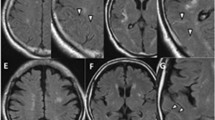

Carotid MR images of a 65-year-old male with left hemiparesis, who was detected to have right ICA 80% stenosis (arrows). His NIHS at admission was 6, with a total of 2 cerebrovascular events before surgery. TOF images (a, b) showing right ICA stenosis with axial TOF showing a largely preserved periluminal dark band indicative of intact fibrous cap. T1 image (c) showed mildly increased signal with T2 (d) and PD (e), showing the plaque to have largely similar intensities. T2 FS (f) also showed the luminal stenosis with DWI image (g) with an ADC value of 1.290 × 10–3 mm2/s (inset in g)